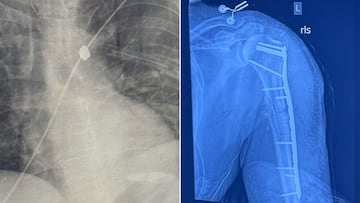

Pese a la gravedad de las heridas, Roberts logró sobrevivir gracias a una intervención médica inmediata. Fue sometido a cirugía el 17 de noviembre para colocar placas de metal en su brazo izquierdo, que quedó destrozado. Sin embargo, los médicos no han podido extraer la bala alojada en su cuerpo debido al riesgo que implicaría.

Su hermana política, Julie Roberts, describió el caso como “una misericordia de Dios”. Según explicó en una campaña de GoFundMe creada para cubrir los costos médicos, “si la bala no hubiese impactado su húmero, probablemente habría perforado su aorta”.